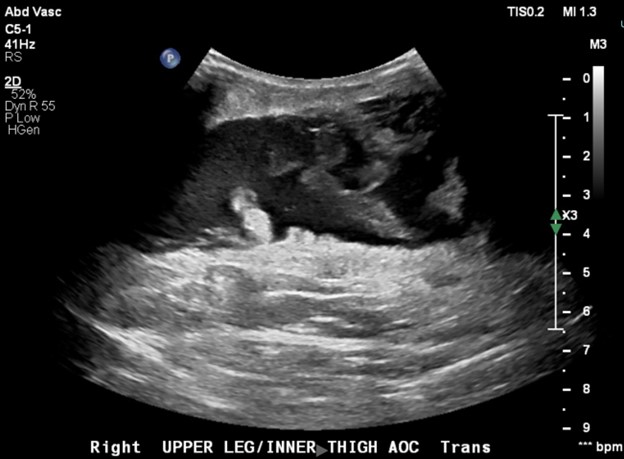

Ultrasound showed a large, elongated fluid collection within the subcutaneous soft tissues of the upper medial thigh at the site of concern measuring 24 cm longitudinal x 2.8 cm transverse, characterized by irregular margins, low level internal echoes that swirled upon compression, and irregular linear internal echogenic foci that may have reflected fat. These findings were consistent with a Morel-Lavallée degloving injury.